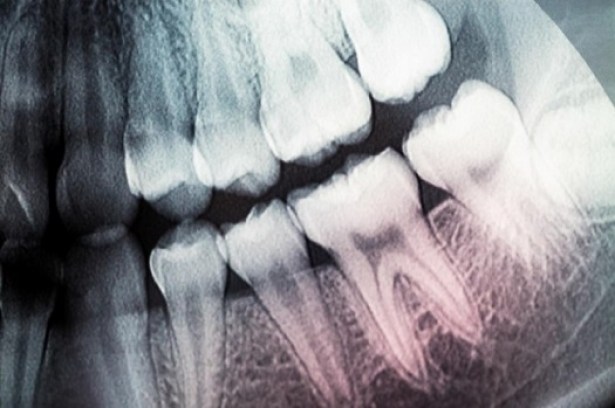

Geçtiğimiz günlerde Science Translational Medicine dergisinde yayınlanan makalede anlatılan ve dişin yeniden büyümesini sağlayan bu yöntem tıpkı bir bilim kurgu romanından fırlamış gibi duruyor. Araştırmayı gerçekleştiren ekip diş gövdesindeki hücreleri tetiklemek ve dentin adı verilen yapıyı yeniden oluşturmasını sağlamak için düşük güçte lazer ışını kullanmış. Dentin, oldukça sert, kemik benzeri bir yapı. Diş minesinin altında yer alan dentin aynı zamanda diş kütlesinin esas parçasını oluşturuyor.